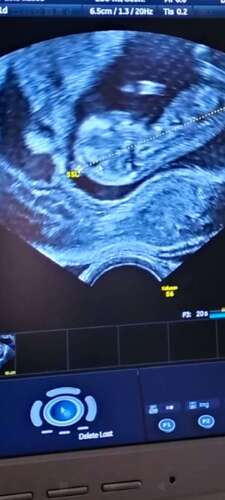

Unser Mäuschen hat total rumgeturnt während der Untersuchung 😍 es hat sich an der Gebärmutter abgedrückt und ist rumgehupft und auch in die Luft geboxt, es war einfach herrlich zuzuschauen. Unser ET wurde 10 Tage vorverlegt 😁😁❤️ sind sehr happy. Hoffe nur noch der NIPT ist unauffällig 🙏

Achja wir sind von 10+6 auf 12+2 gerutscht... Plötzlich im 2. Trimester od ...